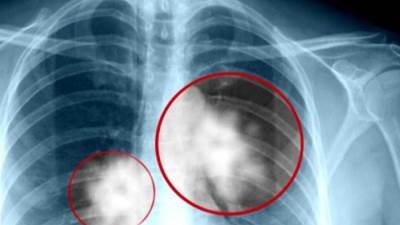

دراسة تعطي أملًا جديدًا لمريضات سرطان الثدي